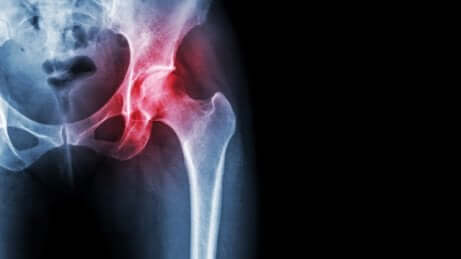

Nécrose avasculaire de la tête fémorale

La nécrose avasculaire, comme toutes les nécroses, est causée par un manque d’apport sanguin aux tissus. Dans ce cas particulier, elle affecte les os, ce qui a un certain nombre de conséquences assez graves.